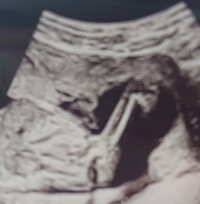

妊娠8週目,8w,妊娠八週,8w0d,8w1d,8w2d,8w3d,8w4d,8w5d,8w6d これまで「胎芽」と呼ばれていましたが、「胎児」と呼ばれるように